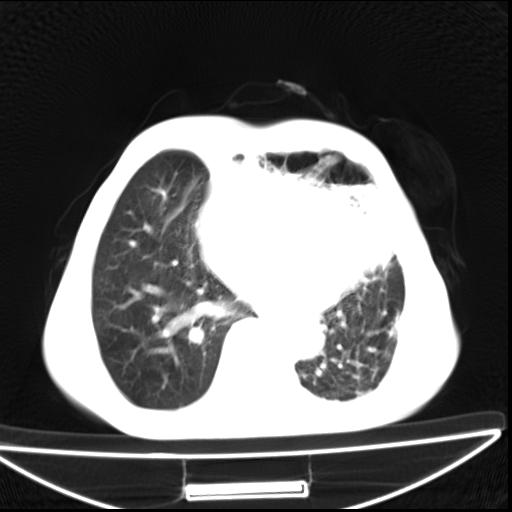

男  70岁,发烧咳嗽4天。盗汗,消瘦。无痰中带血丝,以前有肺tb病史,ct见,双肺tb,左侧胸廓塌陷,左胸膜肥厚粘连。纵隔移位,右侧胸腔积液,大家说说那个心影前左肺舌叶除了肺大炮还有炎症还是干酪性肺炎?有占位吗?我看纵隔淋巴结也大。

1)两肺继发性肺结核并左肺上叶肺不张,支气管扩张。2)双侧胸膜炎(胸膜增厚+少量胸腔积液)。

两肺继发性肺结核并感染,左肺上叶肺不张。建议ct增强。